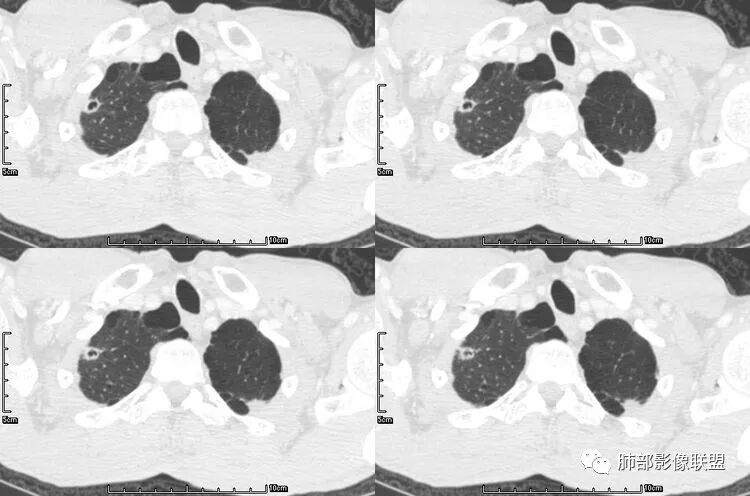

肺腺癌伴双肺转移,双肺多发环形薄壁囊腔转移瘤;

来源于南京大学医学院鼓楼医院 周科峰

本病例左肺下叶肿块,有深分叶、毛刺、胸膜牵拉凹陷、支气管截断及纵隔内淋巴结肿大等征象,都均支持病灶为恶性,如腺癌,而且叶间裂的多发结节也提示是腺癌来源可能大;双肺多发结节、肿块,大部分病灶有分叶、毛刺及胸膜凹陷的恶性征象,与原发肿瘤本身的性质有关,所以应该与左肺下叶肿块同源,而且双肺多发病灶内空洞也具有多样性;

此病例中空洞形态多样,内壁不光整,有分隔影,周围未见明显卫星灶及钙化灶,结核不太符合;患者病史慢性病史,无明显发热,缺乏中毒临床表现,急性感染基本排除;各种中性粒细胞胞浆抗体阴性,没有鼻窦炎,肾脏等病史,基本排除血管炎;霉菌性空洞常见于免疫机能低下者, 常为空洞、肺炎、伴“ 晕圈”征的结节及支气管扩张合并存在。